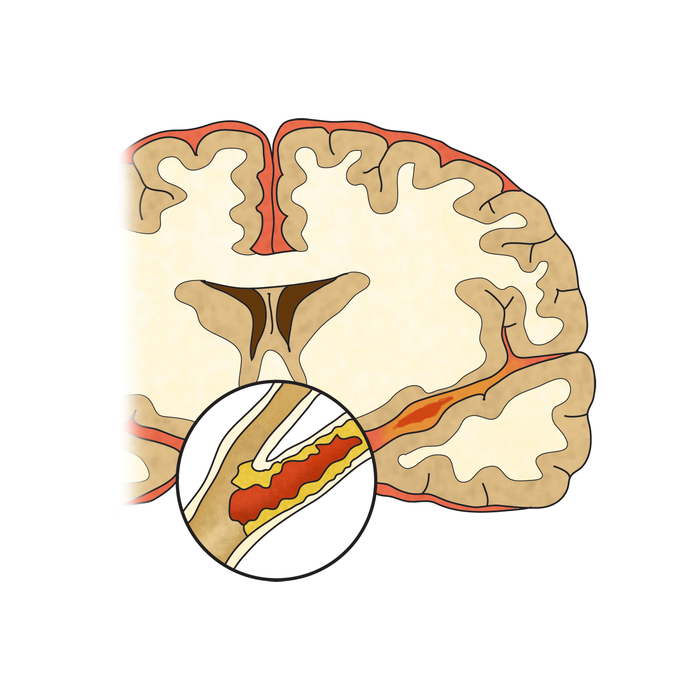

뇌혈류 감소가 일정 시간 이상 계속되면 뇌조직의 괴사가 시작되어요. 뇌조직이 괴사 되어 회복 불가능한 상태에 이르렀을 때 이를 뇌경색이라고하고요. 반면 뇌혈류 감소에 의해 뇌기능에 이상이 생겼지만, 적절한 치료를 통해 넉넉한 뇌혈류가 다시 보급되어 뇌조직의 괴사 없이 뇌기능이 회복된 경우를 일과성 허혈성 발작이라고 불리워요. 허혈성 뇌졸중은 뇌경색과 일괄성 허혈성 발작을 모두 다 포함해서서 일컫는 용어이예요.

뇌조직은 평소에도 거량 물량의 피를 공급받고 있고요. 근데 수많은 이유으로 인해서 뇌혈관에 혈관 등을 이루는 관이 막히는 경우가 일으켜서 뇌에 공급되는 혈액량이 줄어들게 보면 뇌조직이 기능을 정확히 하지 못하게 돼요.